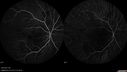

13 year old who was hit in the right eye with a softball about 2 years ago. Pain but no vision loss then. Got "blurry" OD about 5-6 months ago VA OD: Dcc20/40-2 NccJ2 VA OS: Dcc20/20

Choroidal Osteoma 13 Year Old565 views13 year old with 6 months of vision loss right eye and vision of 20/4000000